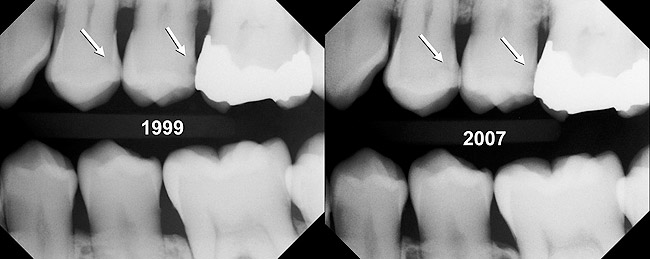

Some may argue that this treatment is supervised neglect or undertreatment. In the past, without good risk assessment and effective management of the biofilm disease, that may have been the case. With the current (and improving) understanding about the management of a biofilm imbalance and the use of risk assessment, this is no longer the case. As an example, a patient presented in 1999 with 2 interproximal radiographic lesions on teeth Nos. 12 and 13 (Figure 7). The radiographs are only a snapshot in time. By understanding the patient’s risk profile, immediate treatment was not indicated. This decision has been validated by examination of her radiographs from 2007, which show these lesions were from a historic cariogenic episode and were no longer progressing.

Figure 7  Nonprogression lesions in a patient who is currently at low risk, although it is obvious that there had been a period of high risk.

Figure 7